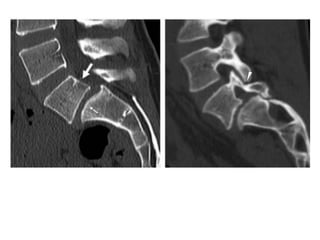

TACY RM

• Lesión unilateral o bilateral

• Seguimiento de espondilólisis

• Estado del defecto

• Morfología

• Evaluación de partes blandas

• Detección precoz de

espondilólisis

TACY RM • Lesiónunilateral o bilateral • Seguimiento de espondilólisis • Estado del defecto • Morfología • Evaluación de partes blandas • Detección precoz de espondilólisis